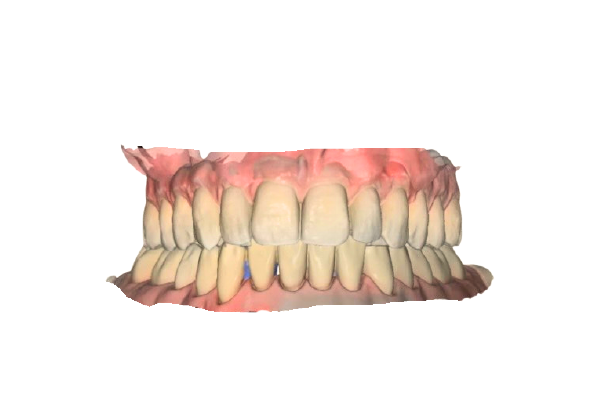

Straumann社製 口腔内スキャナー

「SIRIOS」による精密診断

当院では、世界的歯科メーカーである

Straumann(ストローマン)社の口腔内スキャナー「SIRIOS」を導入しています。

高精度3Dスキャンにより、歯並びや噛み合わせを立体的に確認できます。

従来の粘土のような型取りは不要で、短時間で負担の少ない検査が可能です。

取得したスキャンデータをもとに、治療計画や仕上がりのイメージを

モニター画面で分かりやすくご説明いたします。